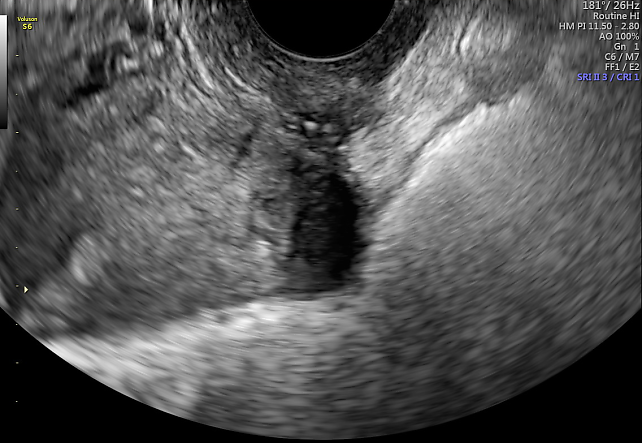

4

Ultrasound image of focal adenomyosis with a hypoechogenic nodule in the posterior outer myometrium, adherent to the distal bowel.